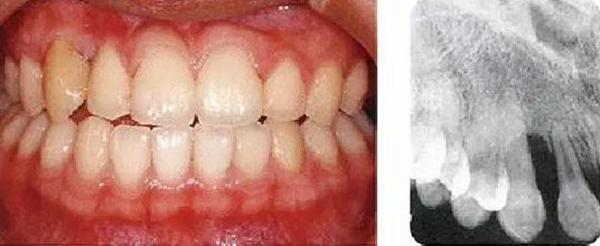

●參考病例② 25歲女性

25歲女性。菌斑控制狀態(tài)不好。齦溝除磨牙處外全在3mm以下,X光照片上左上、右下、左下的第一磨牙上有垂直性骨吸收。這個(gè)病例是參考病例①10年前的狀態(tài),是典型的侵襲性牙周炎局部型。